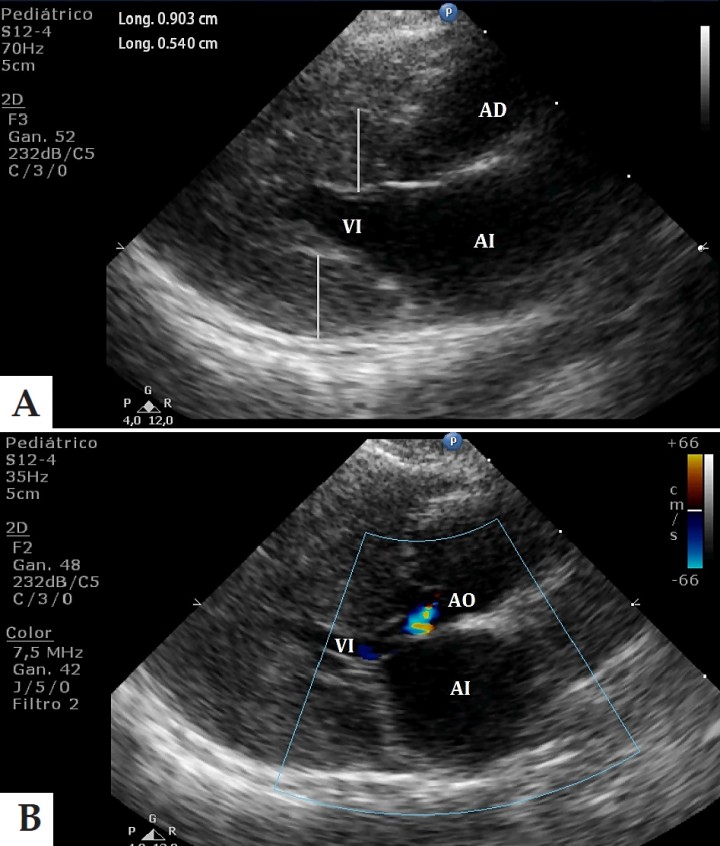

Una vez el patrón respiratorio del paciente cambió, disminuyendo las rpm hasta 24, se realizaron radiografías de tórax, donde se visualizó un leve aumento de la silueta cardíaca, con un índice vertebral cardíaco de 9,5 (siendo normal en gatos hasta un valor de 8), así como edema intersticial perihiliar moderado. Tras estos hallazgos y la presencia del soplo cardíaco, se decidió realizar una ecocardiografía, donde se observó en el ventrículo izquierdo, una hipertrofia concéntrica que afectaba tanto al septo interventricular como a la pared libre, así como una dilatación de la aorta ascendente. El Doppler color mostró un flujo turbulento en el tracto de salida del ventrículo izquierdo y un flujo de regurgitación aórtico (Fig. 1).

<p>A: Imagen ecocardiográfica en un corte paraesternal derecho en eje largo donde se aprecia la hipertrofia de las paredes del ventrículo izquierdo (AI: aurícula izquierda; VI: ventrículo izquierdo; AO: aorta). B: Imagen ecocardiográfica en modo Doppler color en un corte paraesternal derecho en eje largo donde se observa regurgitación en la válvula aórtica debida a la hipertensión sistémica (AI: aurícula izquierda; VI: ventrículo izquierdo; AD: aurícula derecha).</p>

A: Imagen ecocardiográfica en un corte paraesternal derecho en eje largo donde se aprecia la hipertrofia de las paredes del ventrículo izquierdo (AI: aurícula izquierda; VI: ventrículo izquierdo; AO: aorta). B: Imagen ecocardiográfica en modo Doppler color en un corte paraesternal derecho en eje largo donde se observa regurgitación en la válvula aórtica debida a la hipertensión sistémica (AI: aurícula izquierda; VI: ventrículo izquierdo; AD: aurícula derecha).